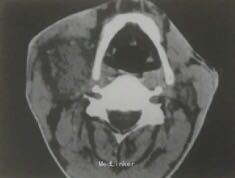

查体示,颈部小包块,不活动,无粘连;CT示颈动脉体区异常密度影,压迫颈动脉窦、颈动脉体区,密度均一,未侵犯其它组织。